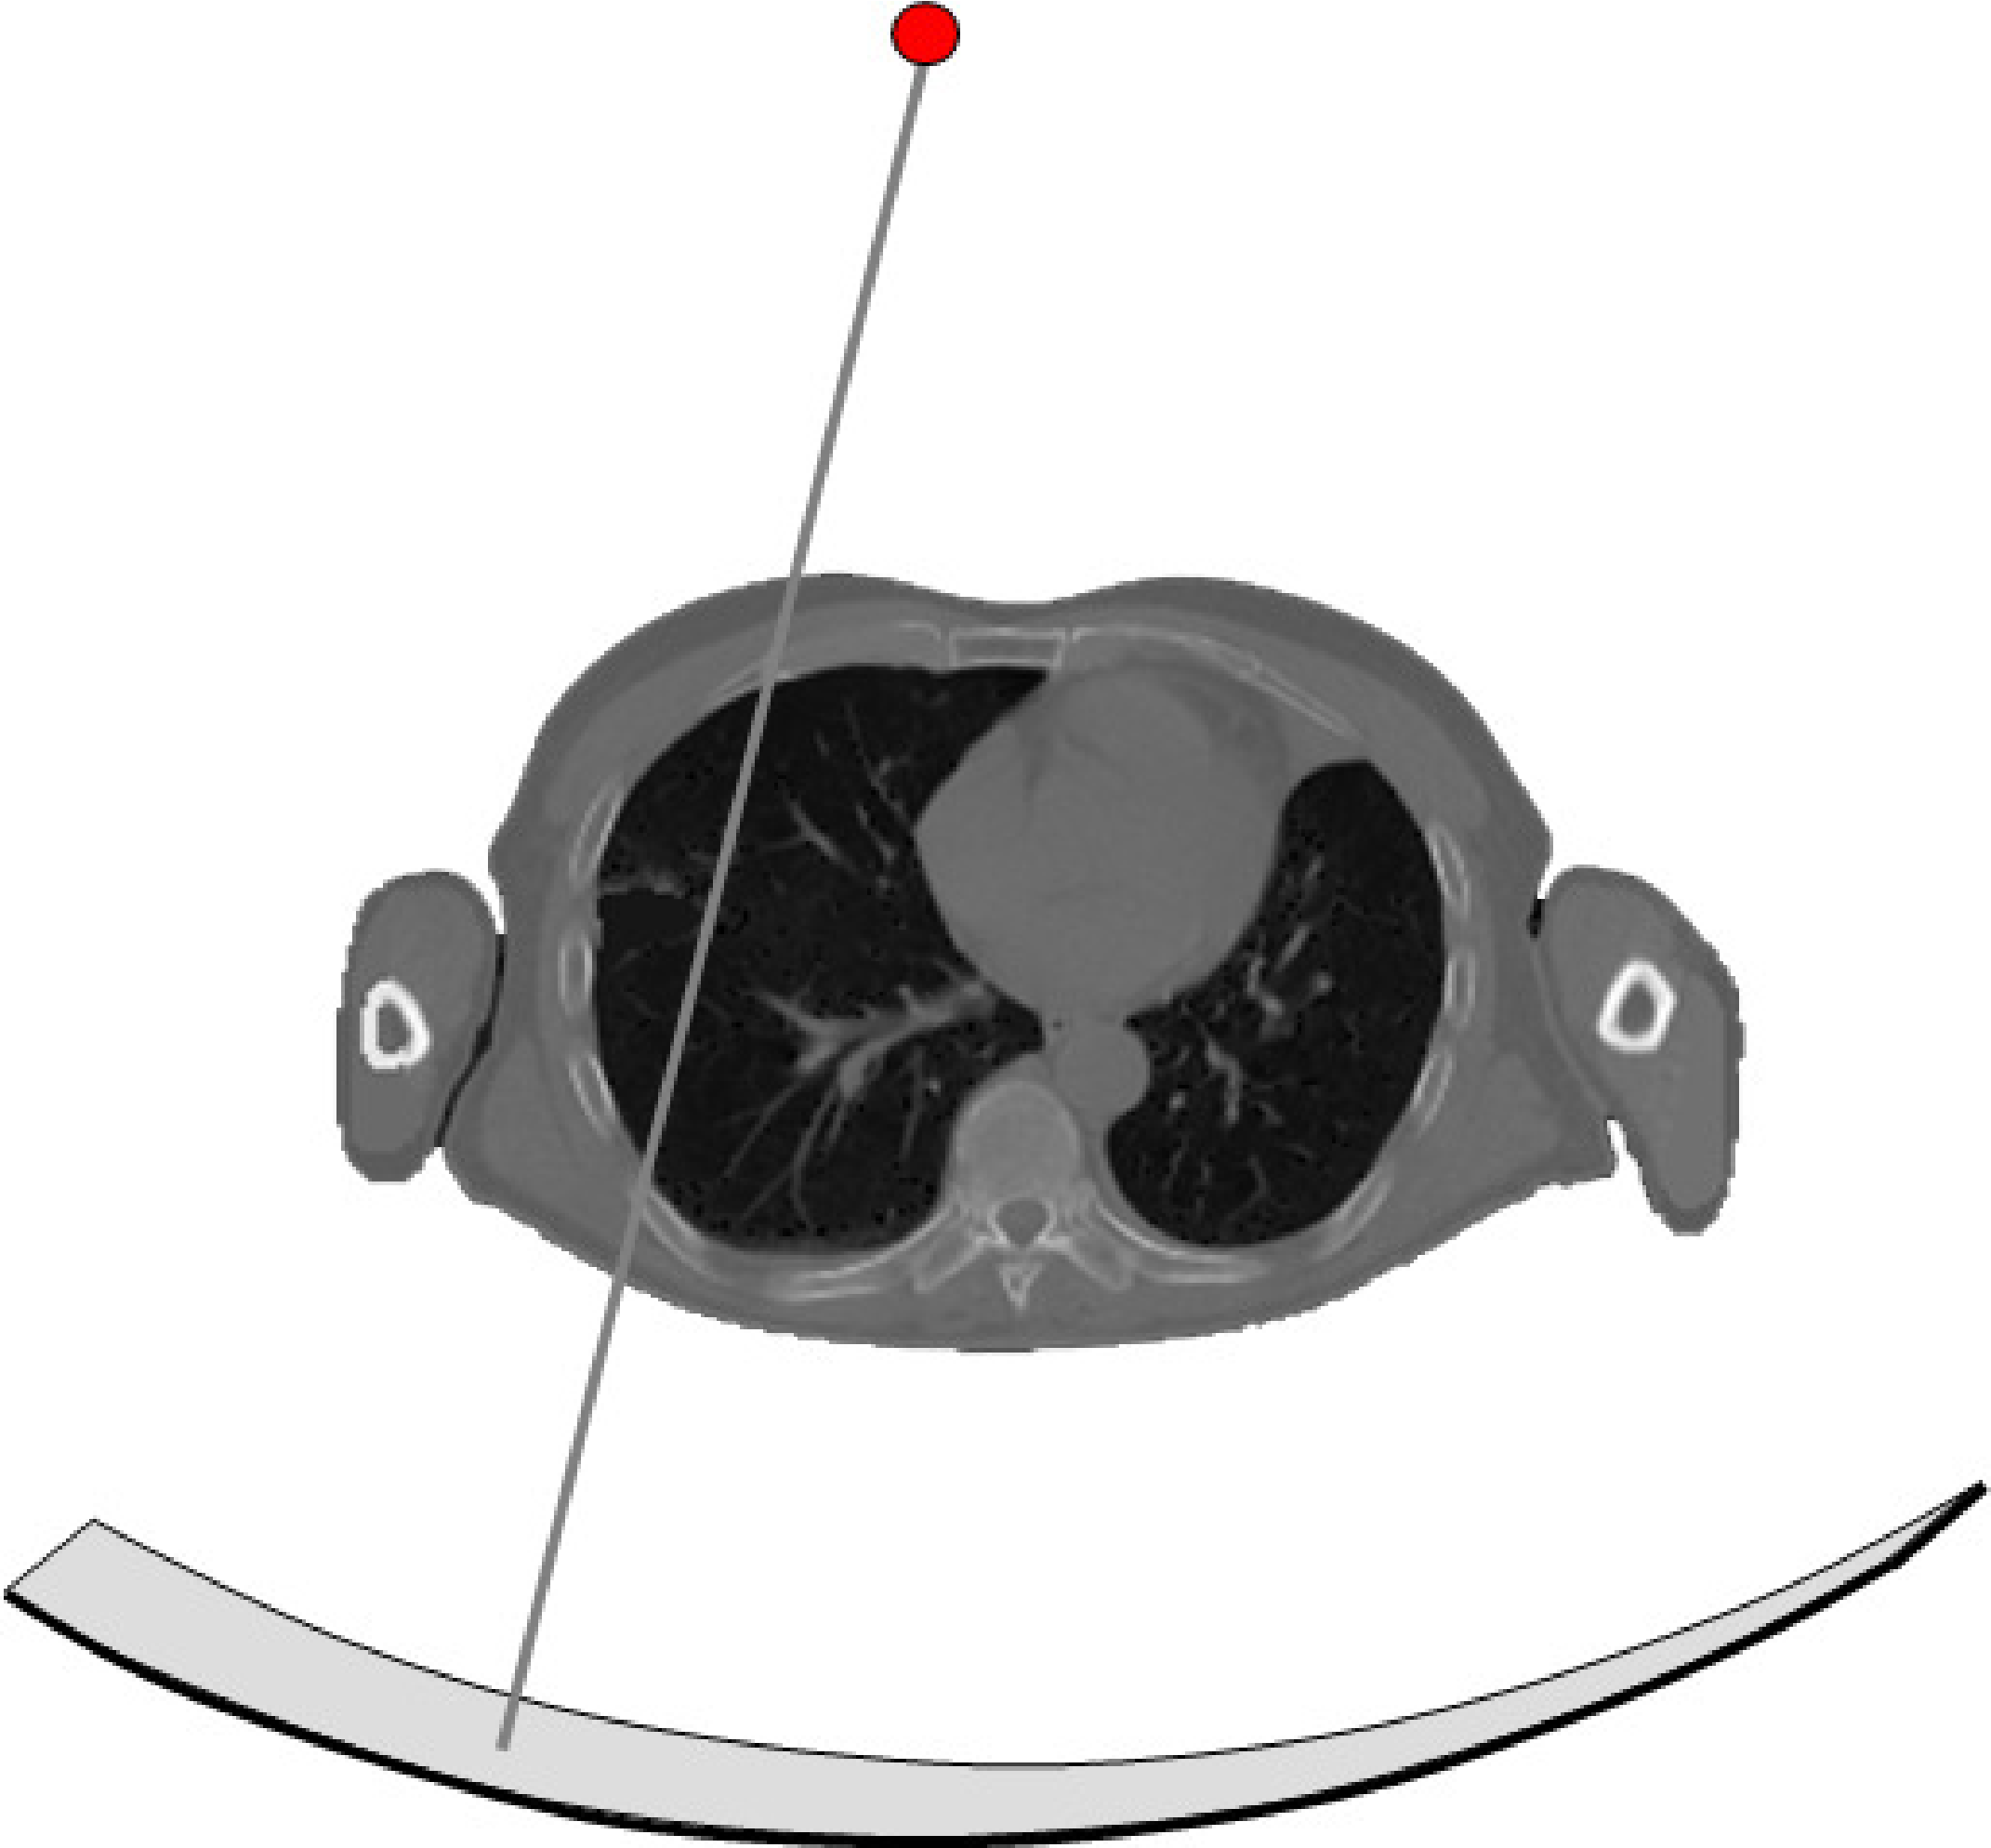

The time between the helical CT-scan and the last PET-scan is about half an hour. That is a long time to ly motionless, and in most PET/CT images one can see small positional mismatches due to patient motion. A similar mismatch is caused by breathing. The CT-scan is very fast compared to the breathing cycle, and essentially takes an image at one point of that cycle. In contrast, the PET-scan runs for a few minutes per bed position, and produces an image averaged over the breathing cycle. This causes motion blur in the PET image, and a registration mismatch with the corresponding CT image. The mismatch may yield attenuation correction artifacts in the PET image. An example of such an artifact is shown in Figure 12. The CT has been taken at maximum inhalation, causing the lungs in the CT-image to be larger than in the PET image. The patient increased his lung size mostly by a displacement of the diaphragm. The CT-based attenuation correction underestimates the attenuation at the dome of the liver (because the computer thinks this part has undergone lung attenuation, and the lungs are far less dense than the liver). This undercorrection, then, yields a decrease of apparent tracer uptake, making the activity in this part of the liver similar to that in the lung. As a result, the liver tumor seems to show up in the lung. The figure also shows an image obtained with attenuation correction based on a (well matched) transmission scan with a positron emitter, clearly showing that the tumor is in the liver.

Figure 12:PET/CT attenuation artifact due to breathing. The tumor is really located in the liver, but the mismatch with the CT and the resulting attenuation correction errors make it show up in the lung.This figure is from a paper by Sarikaya, Yeung, Erdi and Larson, Clinical Nuclear Medicine, 2003; 11: 943